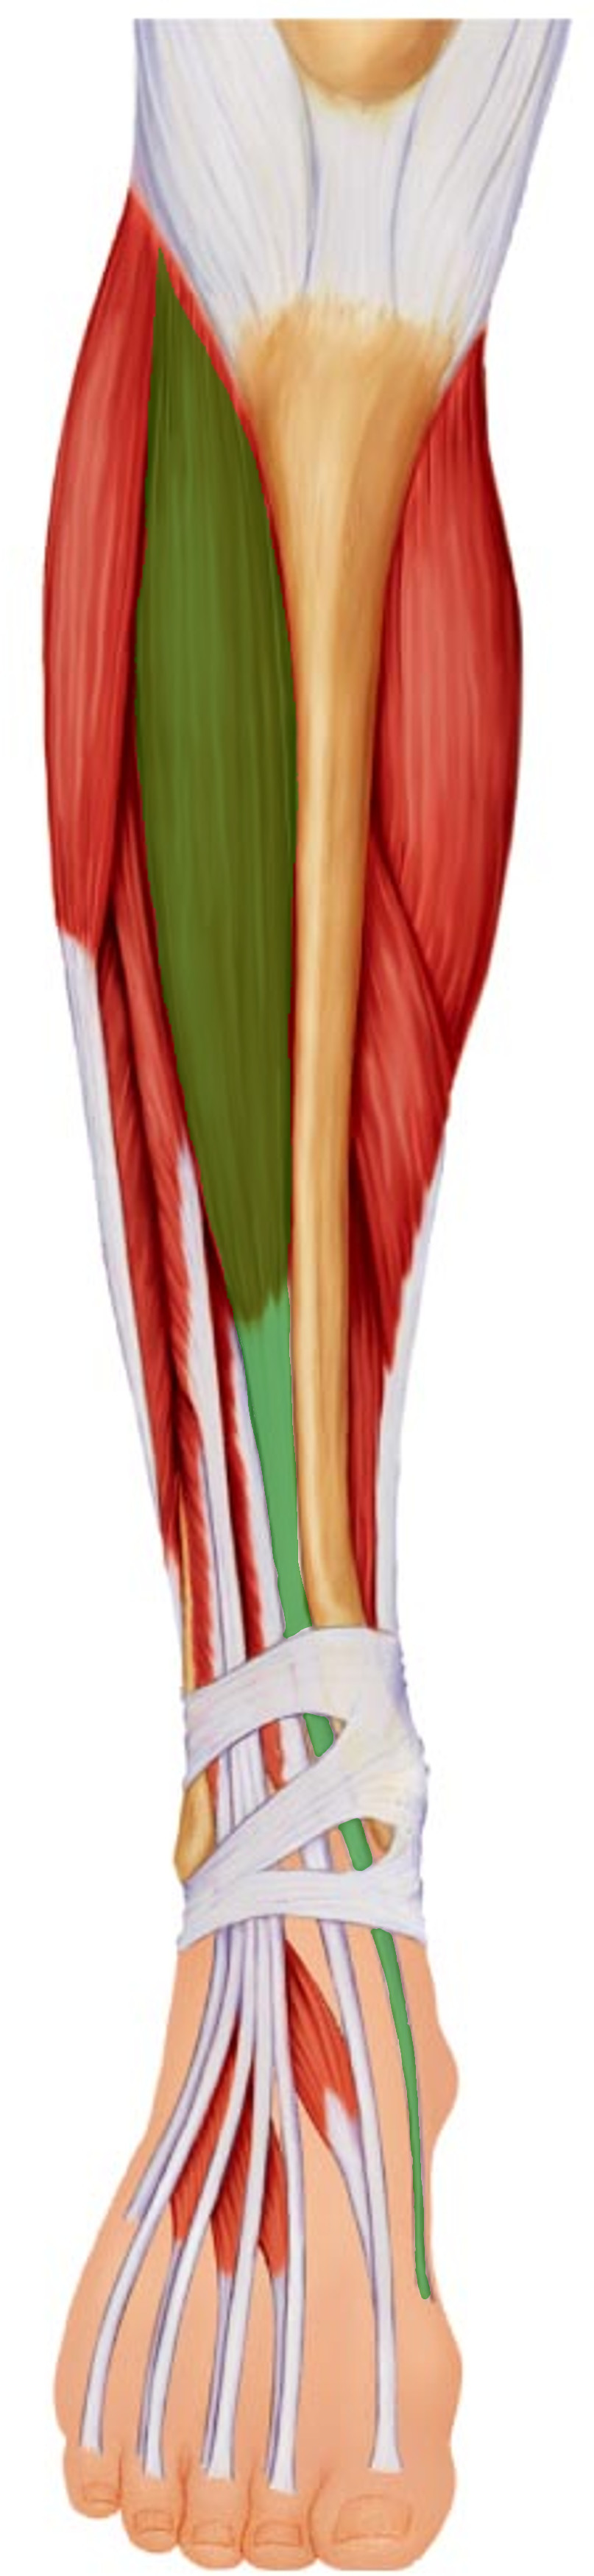

What is the innervation of this muscle?

Muscle - Flexor digitorum longus

Tibial nerve

L5 - S2

What is the innervation of this muscle?

Muscle - Tibialis anterior

Deep fibular nerve

L4 + L5